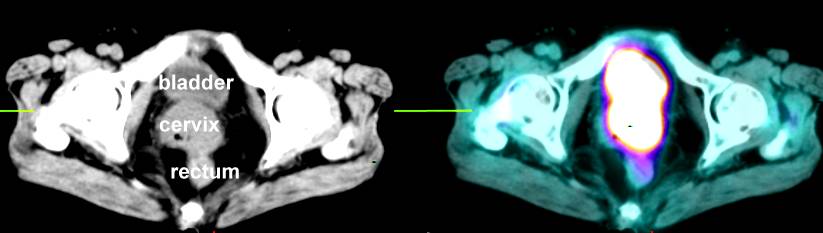

f , Stage IIIb bulky cervix cancer here and here., early stage cervix (IB2) PET here also PET scan uterus here and here and here. PET scan of ovary cancer here. PET scans are good for looking at lymph node spread: go here and here PET scan of vulva cancer that has spread to the right groin lymph nodes is noted below |